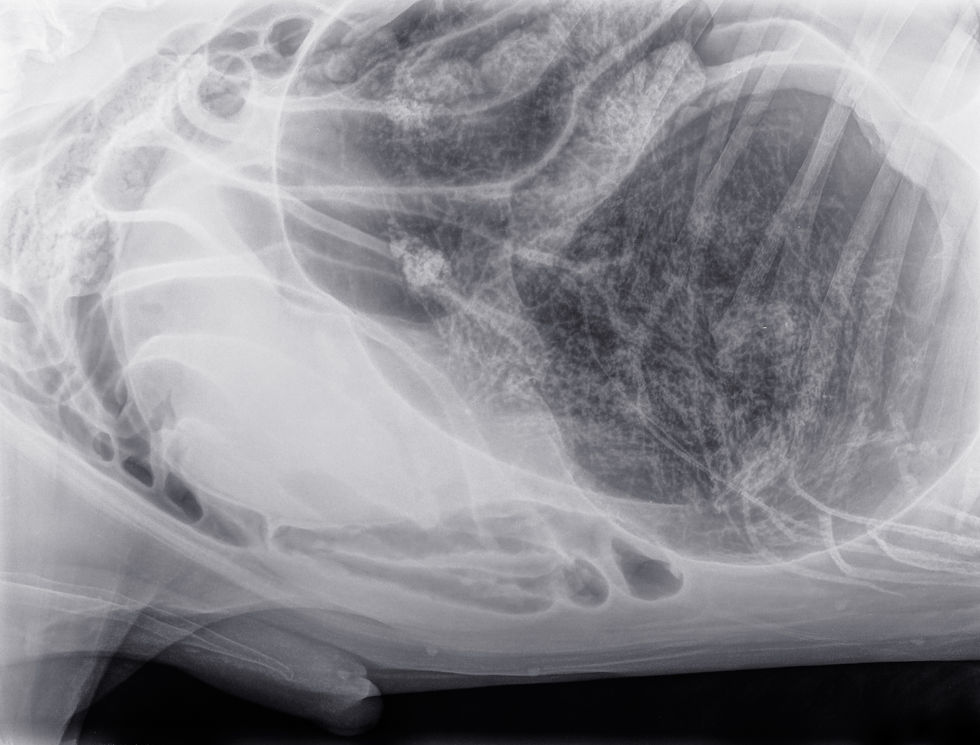

Diagnostic imaging is the cornerstone of differentiating between functional and mechanical ileus. Radiography and ultrasonography provide complementary information. Radiographs of a patient with paralytic ileus typically show a generalized and uniform gaseous or fluid distension of both the small and large intestines. This diffuse pattern is a critical distinction from the focal or segmental dilation seen proximal to a mechanical obstruction (Penninck & d’Anjou, 2015). Other radiographic findings may include a generalized decrease in serosal detail, consistent with abdominal effusion or peritonitis.

Abdominal ultrasonography provides dynamic, real-time information about intestinal motility. The key sonographic criteria for paralytic ileus are the observation of fluid-filled intestinal loops with absent or significantly decreased peristalsis (Firth, 2020). This stands in stark contrast to the non-uniform peristalsis and "pendulous movement" of ingesta often seen with a mechanical obstruction (Gaschen, 2011). The comparison of these key imaging findings is fundamental to clinical decision-making.

Radiography | Generalized, uniform gaseous distension of the large and small intestines | Focal or segmental dilation of intestinal loops proximal to the obstruction site |

Ultrasonography | Fluid-filled loops with absent or decreased peristaltic activity | Non-uniform peristalsis and pendulous movement of ingesta |